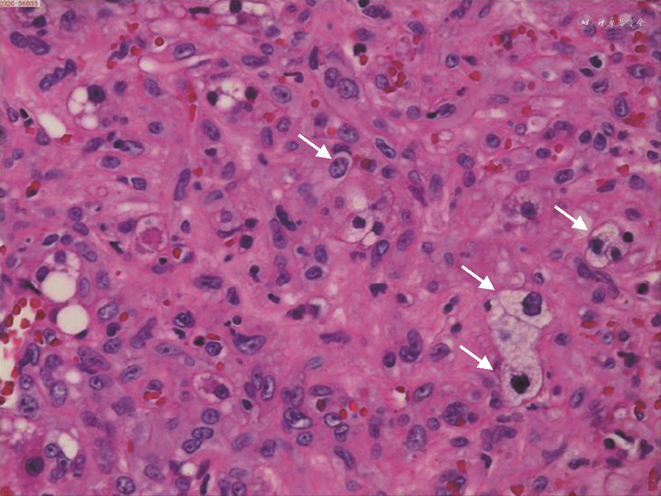

患者女,1963年3月出生,既往体健,曾接种过乙肝疫苗,2011年10月31日因“体检发现肝脏占位10余天”入院。入院时患者无任何不适症状,既往无手术史,无长期药物使用史,无烟酒嗜好,无放射性物质、化学物品等接触史。入院查体:神志清,精神可,营养状态良好,皮肤巩膜未见黄染,无出血点,无肝掌、蜘蛛痣;心肺听诊无殊;全身浅表淋巴结未触及,全腹平软,无压痛、反跳痛,未触及腹部包块,肝脾肋下未及;肝区叩击痛(-),Murphy征(-),移动性浊音(-),肠鸣音4次/min。实验室检查:肝功能正常,乙肝系列检查HBsAb92.83↑、HBcAb0.008↓,其余指标正常;肿瘤标记物CEA、AFP、CAl99、CAl25等均在正常范围内。影像学检查:肝脏B超(本院2011-10-20)显示:右肝及大小约3.0 cm×3.0 cm×3.6 cm实质偏低回声结节区,边界可及;胆脏B超:大小形态正常,壁上及约0.6 cm偏强回声结节,向囊内隆起,胆总管未见明显扩张。提示:右肝实质低回声团块,建议进一步检查;胆囊息肉。全腹部CT平扫+增强(本院2011.10.21)显示:肝脏各叶大小比例正常,肝右叶前上段见一团状低密度影,大小约26 mm×24 mm,边缘略模糊;增强后病灶边缘略强化,延迟后病灶有缩小,肝内外胆管不扩张。上腹部MR平扫+增强(本院2011-10-25)显示:肝脏各叶大小比例正常,肝右叶前上段见一团块异常信号灶,大小约29 mm×31 mm,T1低信号,T2高信号,DWI稍高信号;增强早期病灶边缘强化,延迟后病灶有明显缩小,肝内外胆管不扩张。提示:肝右叶前上段占位,不典型的血管瘤可能,胆管细胞癌不能完全排除,请结合临床建议进一步检查。排除手术禁忌后于2011年11月2日在全身麻醉下行右肝部分切除术,术中见肿块位于右肝第Ⅶ段,大小2.0 cm×3.0 cm、色灰白、质地硬,累及肝脏表面,决定行右肝部分切除术。术后常规病理(本院2011-11-09)示:(右肝)上皮样血管内皮瘤(低-中度恶性)(图1)。免疫组化:本院:Vim(+++)、CD34(+++)、CD31(++);HMB-45、S-100、CK7、CK19、CK8/18均(-);浙江大学医学院第一附属医院:CK(+/-)、CK19(-)、Hep(-)、Ki-67(5%+)、CD34、CD31、Fli-1均(+++)。

患者第1次出院后未进行药物治疗,定期在我院或浙江大学医学院第一附属医院复查肝胆B超和(或)上腹部CT,均未发现明显异常。上腹部CT平扫+增强(2018-04-19)影像所见:肝右叶部分切除术后,肝左叶低密度结节影,范围约34 mm×52 mm,边界清;平扫CT值约32 HU,延迟期边缘呈结节样轻度强化,病灶有缩小(图2)。影像诊断及建议:肝右叶部分切除术后;肝左叶占位,血管内皮瘤可能性大,其他病变不除外,请结合临床必要时进一步检查。患者于2018年5月9日第2次入院,实验室检查示:肝功能正常,乙肝系列检查HBsAb48.180↑、HBcAb0.010↓,其余指标正常;肿瘤标记物中CA724 13.94↑,其余肿瘤标记物CEA、AFP、CAl99、CAl25等均在正常范围内。排除手术禁忌后于2018年5月12日行腹腔镜下左肝部分切除术,术中用超声刀游离左肝叶周围组织,用腹腔镜下直线切割闭合器分离离断左肝外叶。术后病理(本院2018-05-16)示:(左肝)上皮样血管内皮瘤(直径6.5 cm)(图3)。免疫组化B片:AFP(-)、CD31(+++)、CD34(+++)、CD19(-)、CK7(-)、CK8/18(-)、D2-40(灶+)、Vim(++)。免疫组化诊断结果:B片:AFP(-)、CD31(+++)、CD34(+++)、CD19(-)、CK7(-)、CK8/18(-)、D2-40(灶+)、Vim(++)。

患者第2次手术后同样未进行药物治疗,仅进行定期复查。全腹部CT平扫+增强(本院2020-11-06)示:尾状叶类圆21 mm×23 mm稍低密度伴轻度强化,肝裂旁稍肿大淋巴结(图4);肝右叶部分切除术后,肝左叶占位术后,请结合临床。肝尾状叶占位灶,转移瘤待排,建议进一步检查。实验室检查(本院2020-11-05)示:肝功能正常,乙肝系列检查HBsAb86.800↑、HBcAb0.010↓,其余指标正常;肿瘤标记物CEA、AFP、CAl99、CAl25、CAl53、CA724等在正常范围内。排除禁忌后于2020年11月7日行复杂肝癌切除术,术中充分暴露肝尾状叶,用超声刀、氩气刀切除肝尾状叶并予以残端止血。切除的尾状叶送病理科行术中冰冻快切病理检查,诊断为(肝脏)上皮样血管内皮瘤。病理组织学诊断结果(本院2020-11-13):(1)(肝脏)上皮样血管内皮瘤(肿块大小2.5 cm×2.0 cm;图5),伴见脉管内瘤栓,切缘阴性,送检(第7、8、9、1、3、12组)3/13个淋巴结见肿瘤细胞转移;(2)部分肝组织;(3)注:该肿瘤组织免疫组化提示CK8/18及AFP阳性,提示该肿瘤存在向上皮成分分化。免疫组化诊断结果:E片:CD31(+++)、CD34(+++)、FLI-1(+++)、CK8/18(+++)、CK19(-)。H片:AFP(+)、CD31(+++)、CD34(+++)、CK19(-)、FLI-1(++)、CK8/18(+)、D2-40(-)、Ki-67(+)15%、Vim(+++)、EMA(-)。